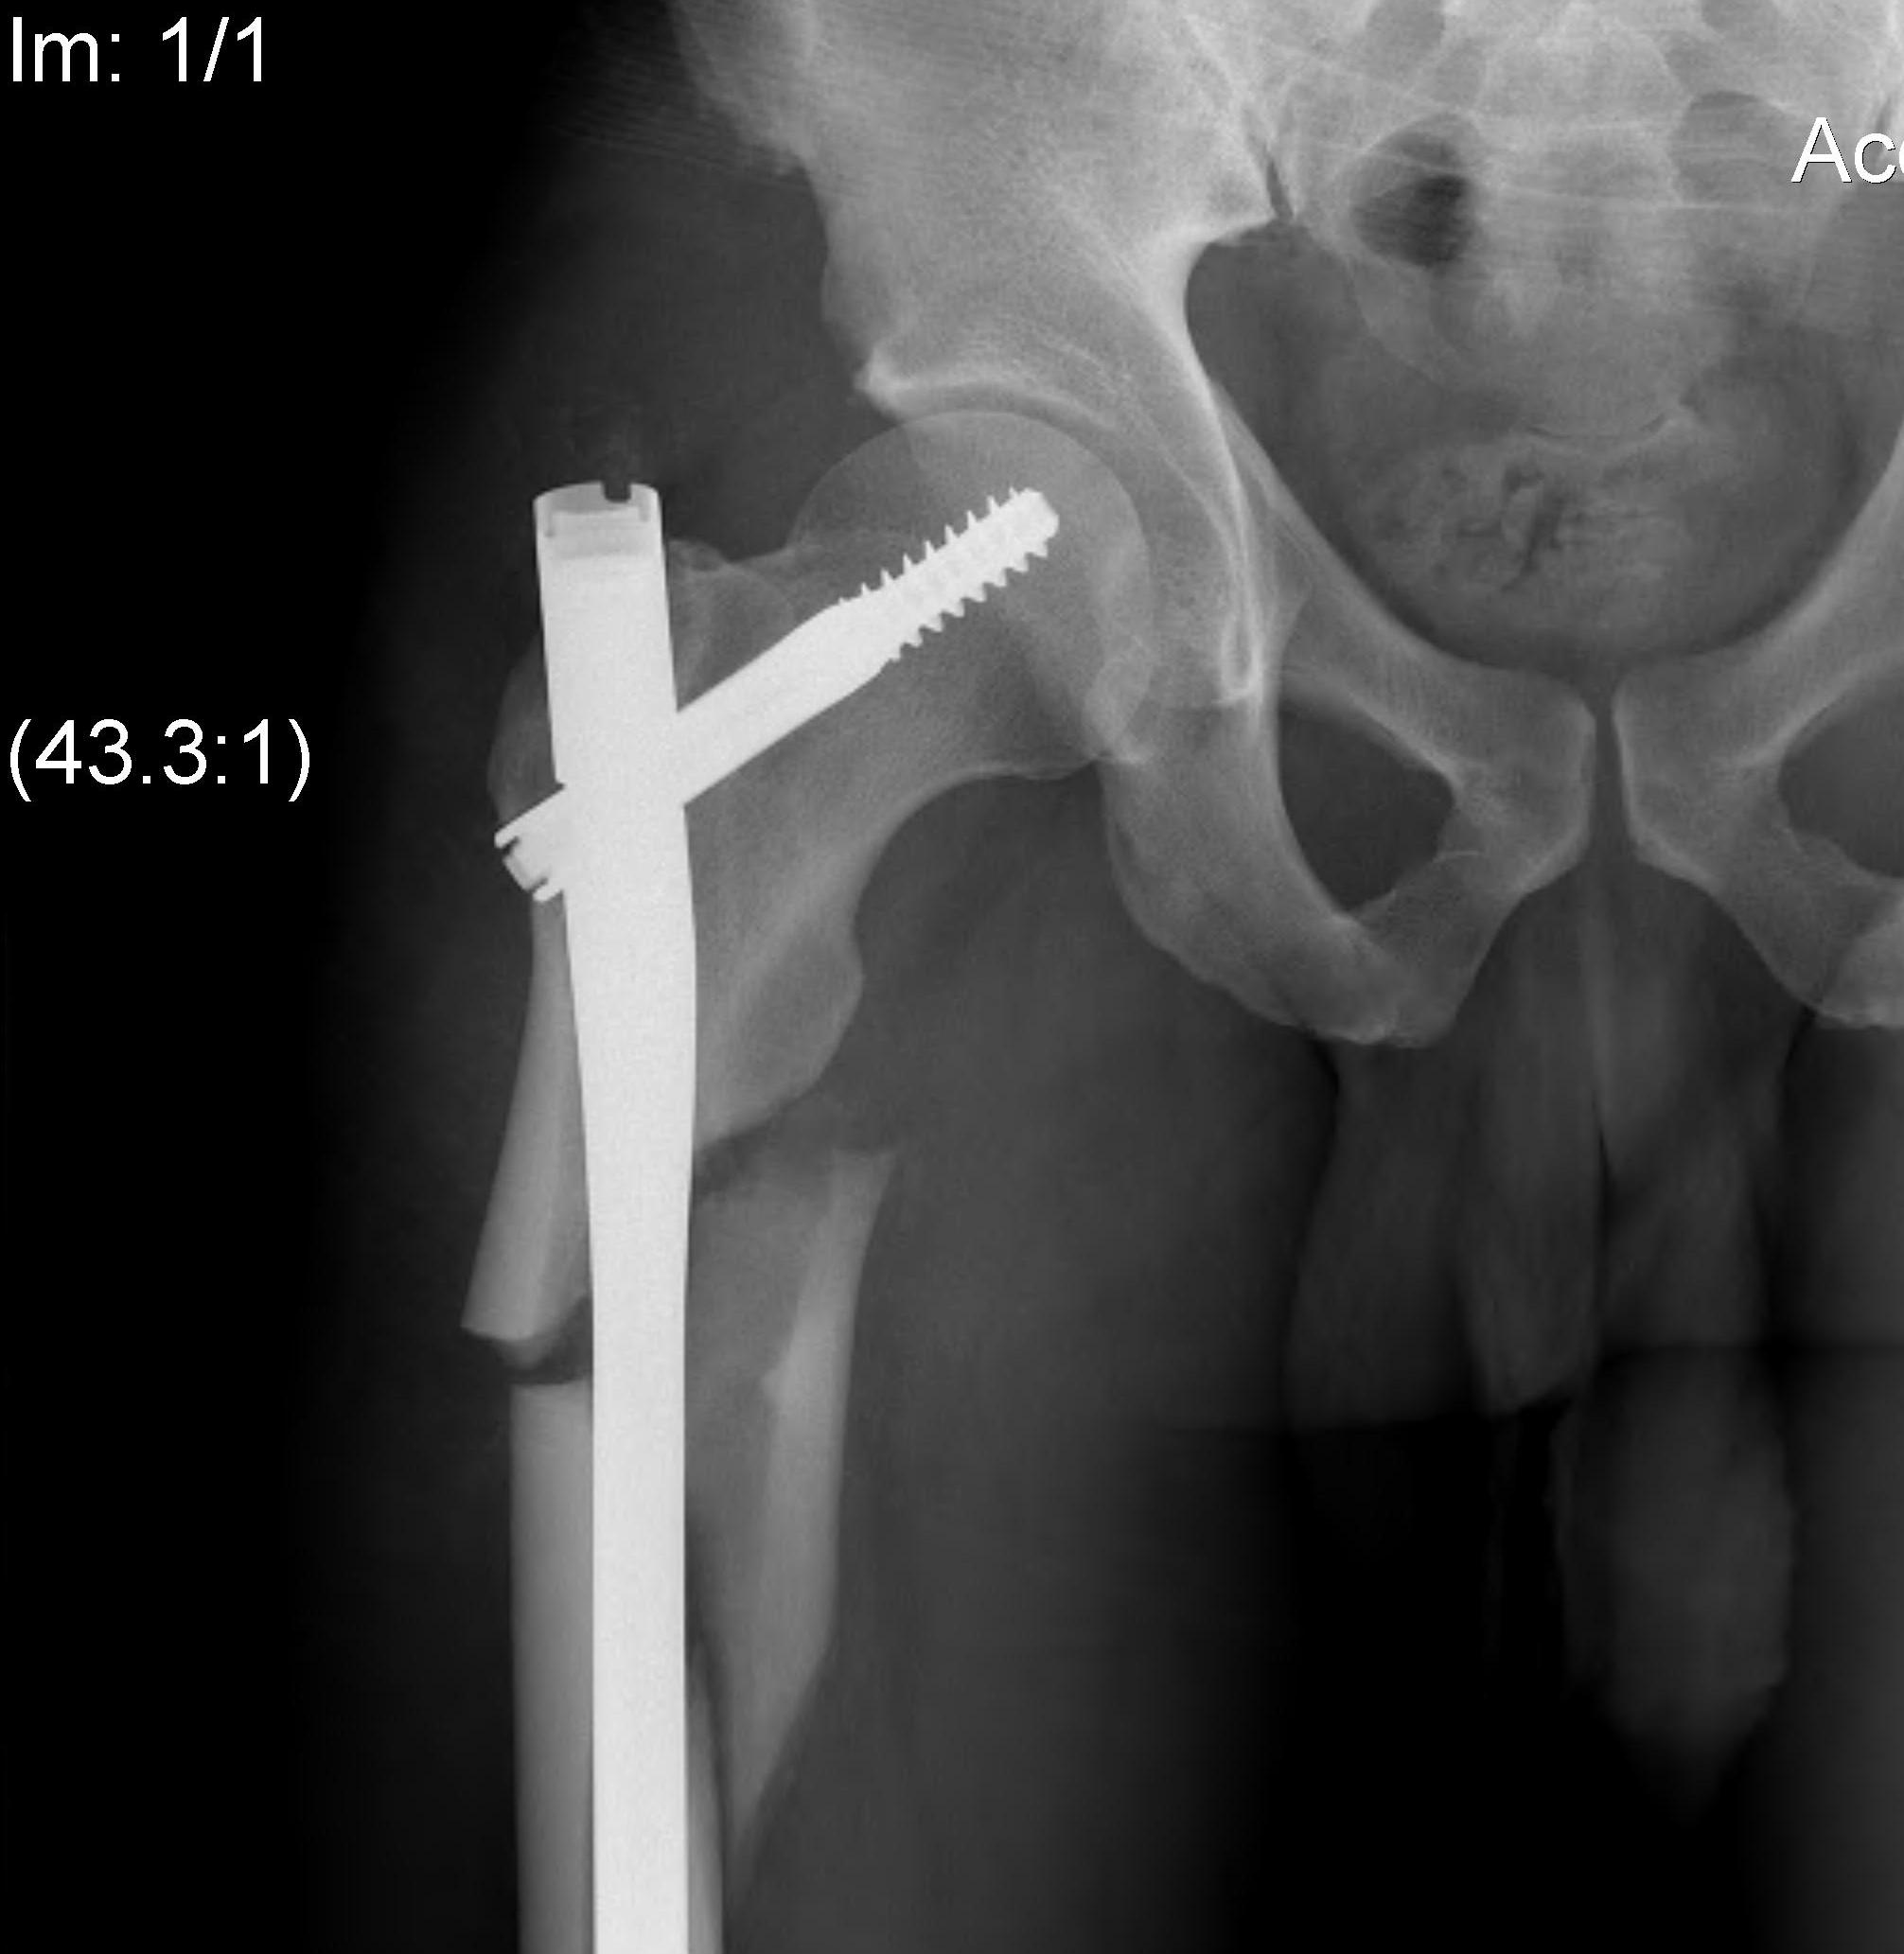

Varus malreduction

Issue

- trendelenberg gait

- LLD

- non union

3. Varus malreduction associated with non union

- anatomical reduction key to union

- all nonunion occurred with varus > 10 degrees